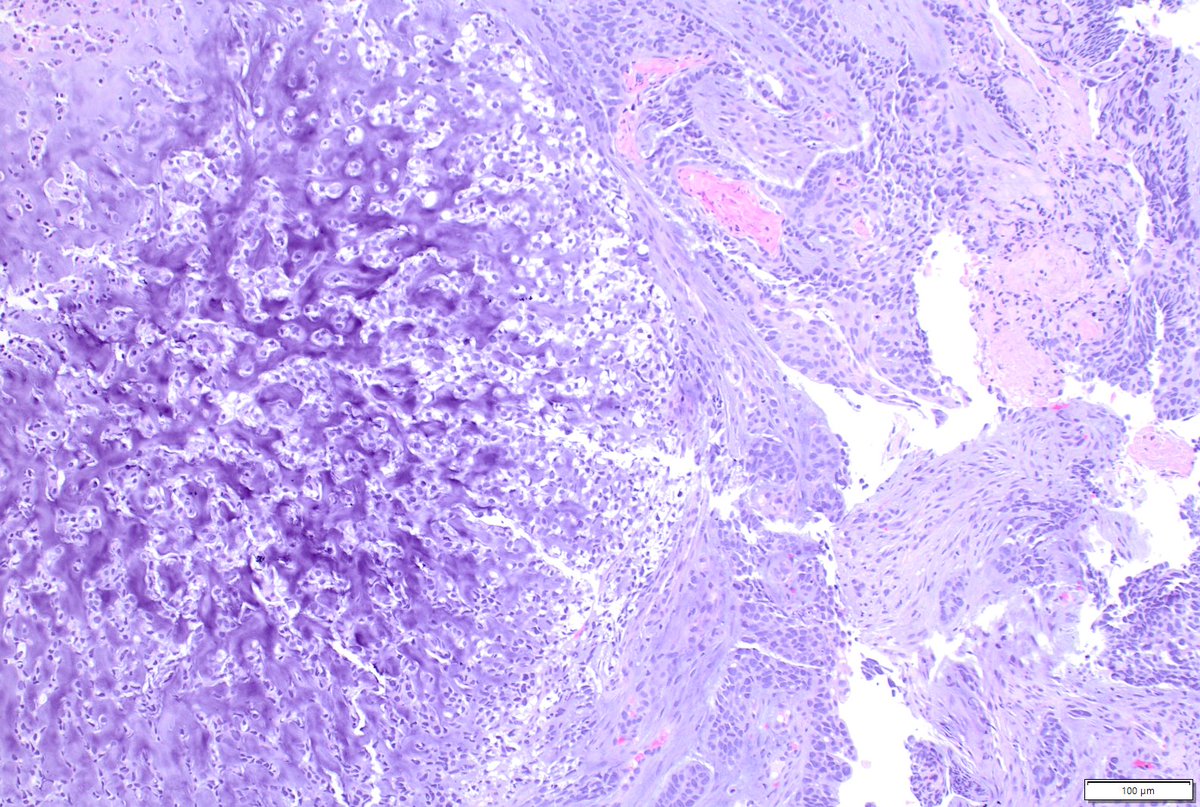

Just out in AJSP – a paper from our group describing a MAJOR new oddity. Tumors that normally arise in the jaw from tooth🦷precursors (ameloblastoma) – but as lung primaries 🫁! This was a neat collaboration b/w MSKCC, Mayo and UTSW where these cases were encountered independently, and we put our heads together with the help of original contributors and fellows to tackle this puzzle. Time will tell if these are truly exceptional or have been underrecognized. journals.lww.com/ajsp/fulltext/… @JLHornick @ENTpathology @MSKPathology @PulmPathSoc @yro854 @thoracicpath @Path_Matt @SansanoValero @AndreMo77438628